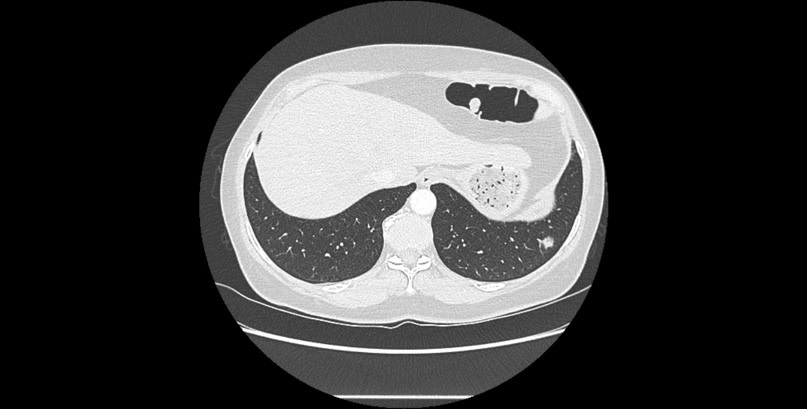

Une femme de 53 ans, ancienne fumeuse (20 paquets-années), sans antécédents médicaux chirurgicaux particuliers est adressée pour une prise en charge chirurgicale diagnostique et thérapeutique d’une lésion pulmonaire lobaire inférieure gauche suspecte. C’est lors d’un scanner abdominal qu’il a été mis en évidence un nodule basal gauche en mars 2024 de 12 mm résistant à une double ligne d’antibiothérapie (Figure 2). Le PET scanner ne retrouve pas d’hypermétabolisme franc suspect en regard de cette image latéro-basale gauche. L’IRM cérébrale ne retrouve pas de lésion suspecte. La fibroscopie bronchique est sans particularité.

Décision thérapeutique

Après un bilan d’opérabilité, l’indication d’une prise en charge chirurgicale diagnostique et thérapeutique à type de segmentectomie intentionnelle a été validée en réunion de concertation pluridisciplinaire pour cette lésion classée cT1bN0M0.